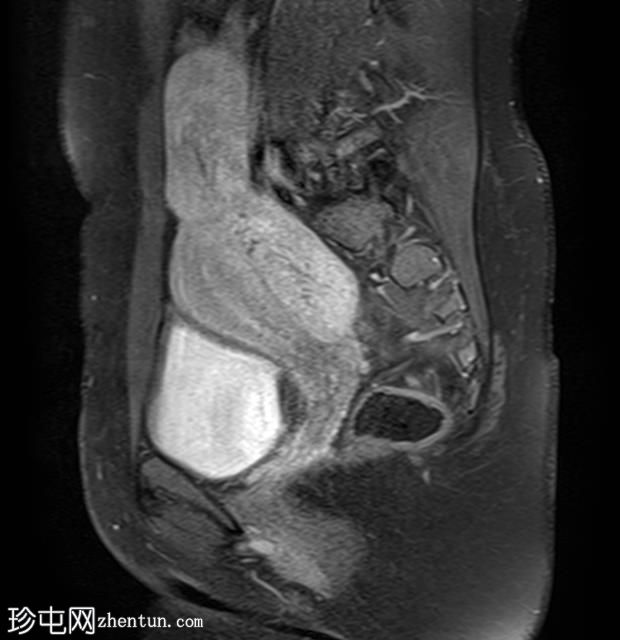

矢状位

T2加权像

其中一个位于子宫上方,T2加权像呈中等信号,中心区域呈高信号,增强T1脂肪抑制像未见强化。右侧卵巢增大,增厚的血管蒂扭曲,未见强化,轴位和矢状位T2加权像均显示清晰。

另一个位于子宫后窝,T2加权像呈中等信号,增强扫描显示明显强化。

轻度腹腔积液